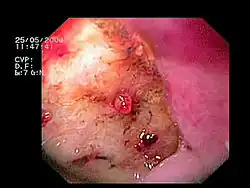

Wrzód żołądka z widocznym sterczącym naczyniem

Choroba wrzodowa żołądka i dwunastnicy jest przyczyną około 50% przypadków krwawienia z górnego odcinka przewodu pokarmowego[19][20][21][22]. U około 15% chorych z chorobą wrzodową rozwija się krwawienie[46]. Choroba wrzodowa jest spowodowana przede wszystkim zakażeniem bakterią Helicobacter pylori, która odpowiada za 95% przypadków wrzodów dwunastnicy i 70% przypadków wrzodów żołądka[47][48]. Choć infekcję Helicobacter pylori w zależności od populacji obserwuje się u około 50–80% osób[49][50], to jednak choroba wrzodowa rozwija się u 6–20% zakażonych[49][48]. Szacuje się, że 20% chorych z obecnym wrzodem trawiennym doświadczy krwawienia z przewodu pokarmowego o różnym nasileniu w przebiegu choroby[51]. Jednak zaobserwowano, że częstość infekcji Helicobacter pylori jest niższa u chorych z krwawiącymi wrzodami niż u chorych z niekrwawiącymi wrzodami[52][49], możliwe więc, że infekcja Helicobacter pylori nie jest czynnikiem ryzyka wystąpienia krwawienia z wrzodu[51]. Z drugiej strony eradykacja zakażenia prowadzi do zmniejszenia ryzyka nawrotu krwawienia[53][54][55][56][57].

Jawne krwawienie z wrzodu jest skutkiem uszkodzenia naczyń krwionośnych przez kwaśną treść żołądkową, drążący w głąb ściany wrzód, choć faktycznie w przypadku każdego wrzodu dochodzi do przewlekłej utraty krwi[65][66]. Ryzyko krwawienia z wrzodu wzrasta u chorych przyjmujących niesteroidowe leki przeciwzapalne[67]. Bardzo rzadko stwierdza się krwawienie z wrzodu bez obecności zakażenia Helicobacter pylori lub stosowania niesteroidowych leków przeciwzapalnych[68]. Krwawienie ustępuje samoistnie w 80% przypadków[66]. Choroba wrzodowa objawia się głównie bólem w nadbrzuszu oraz niestrawnością, choć część chorych nie odczuwa żadnych objawów[20].